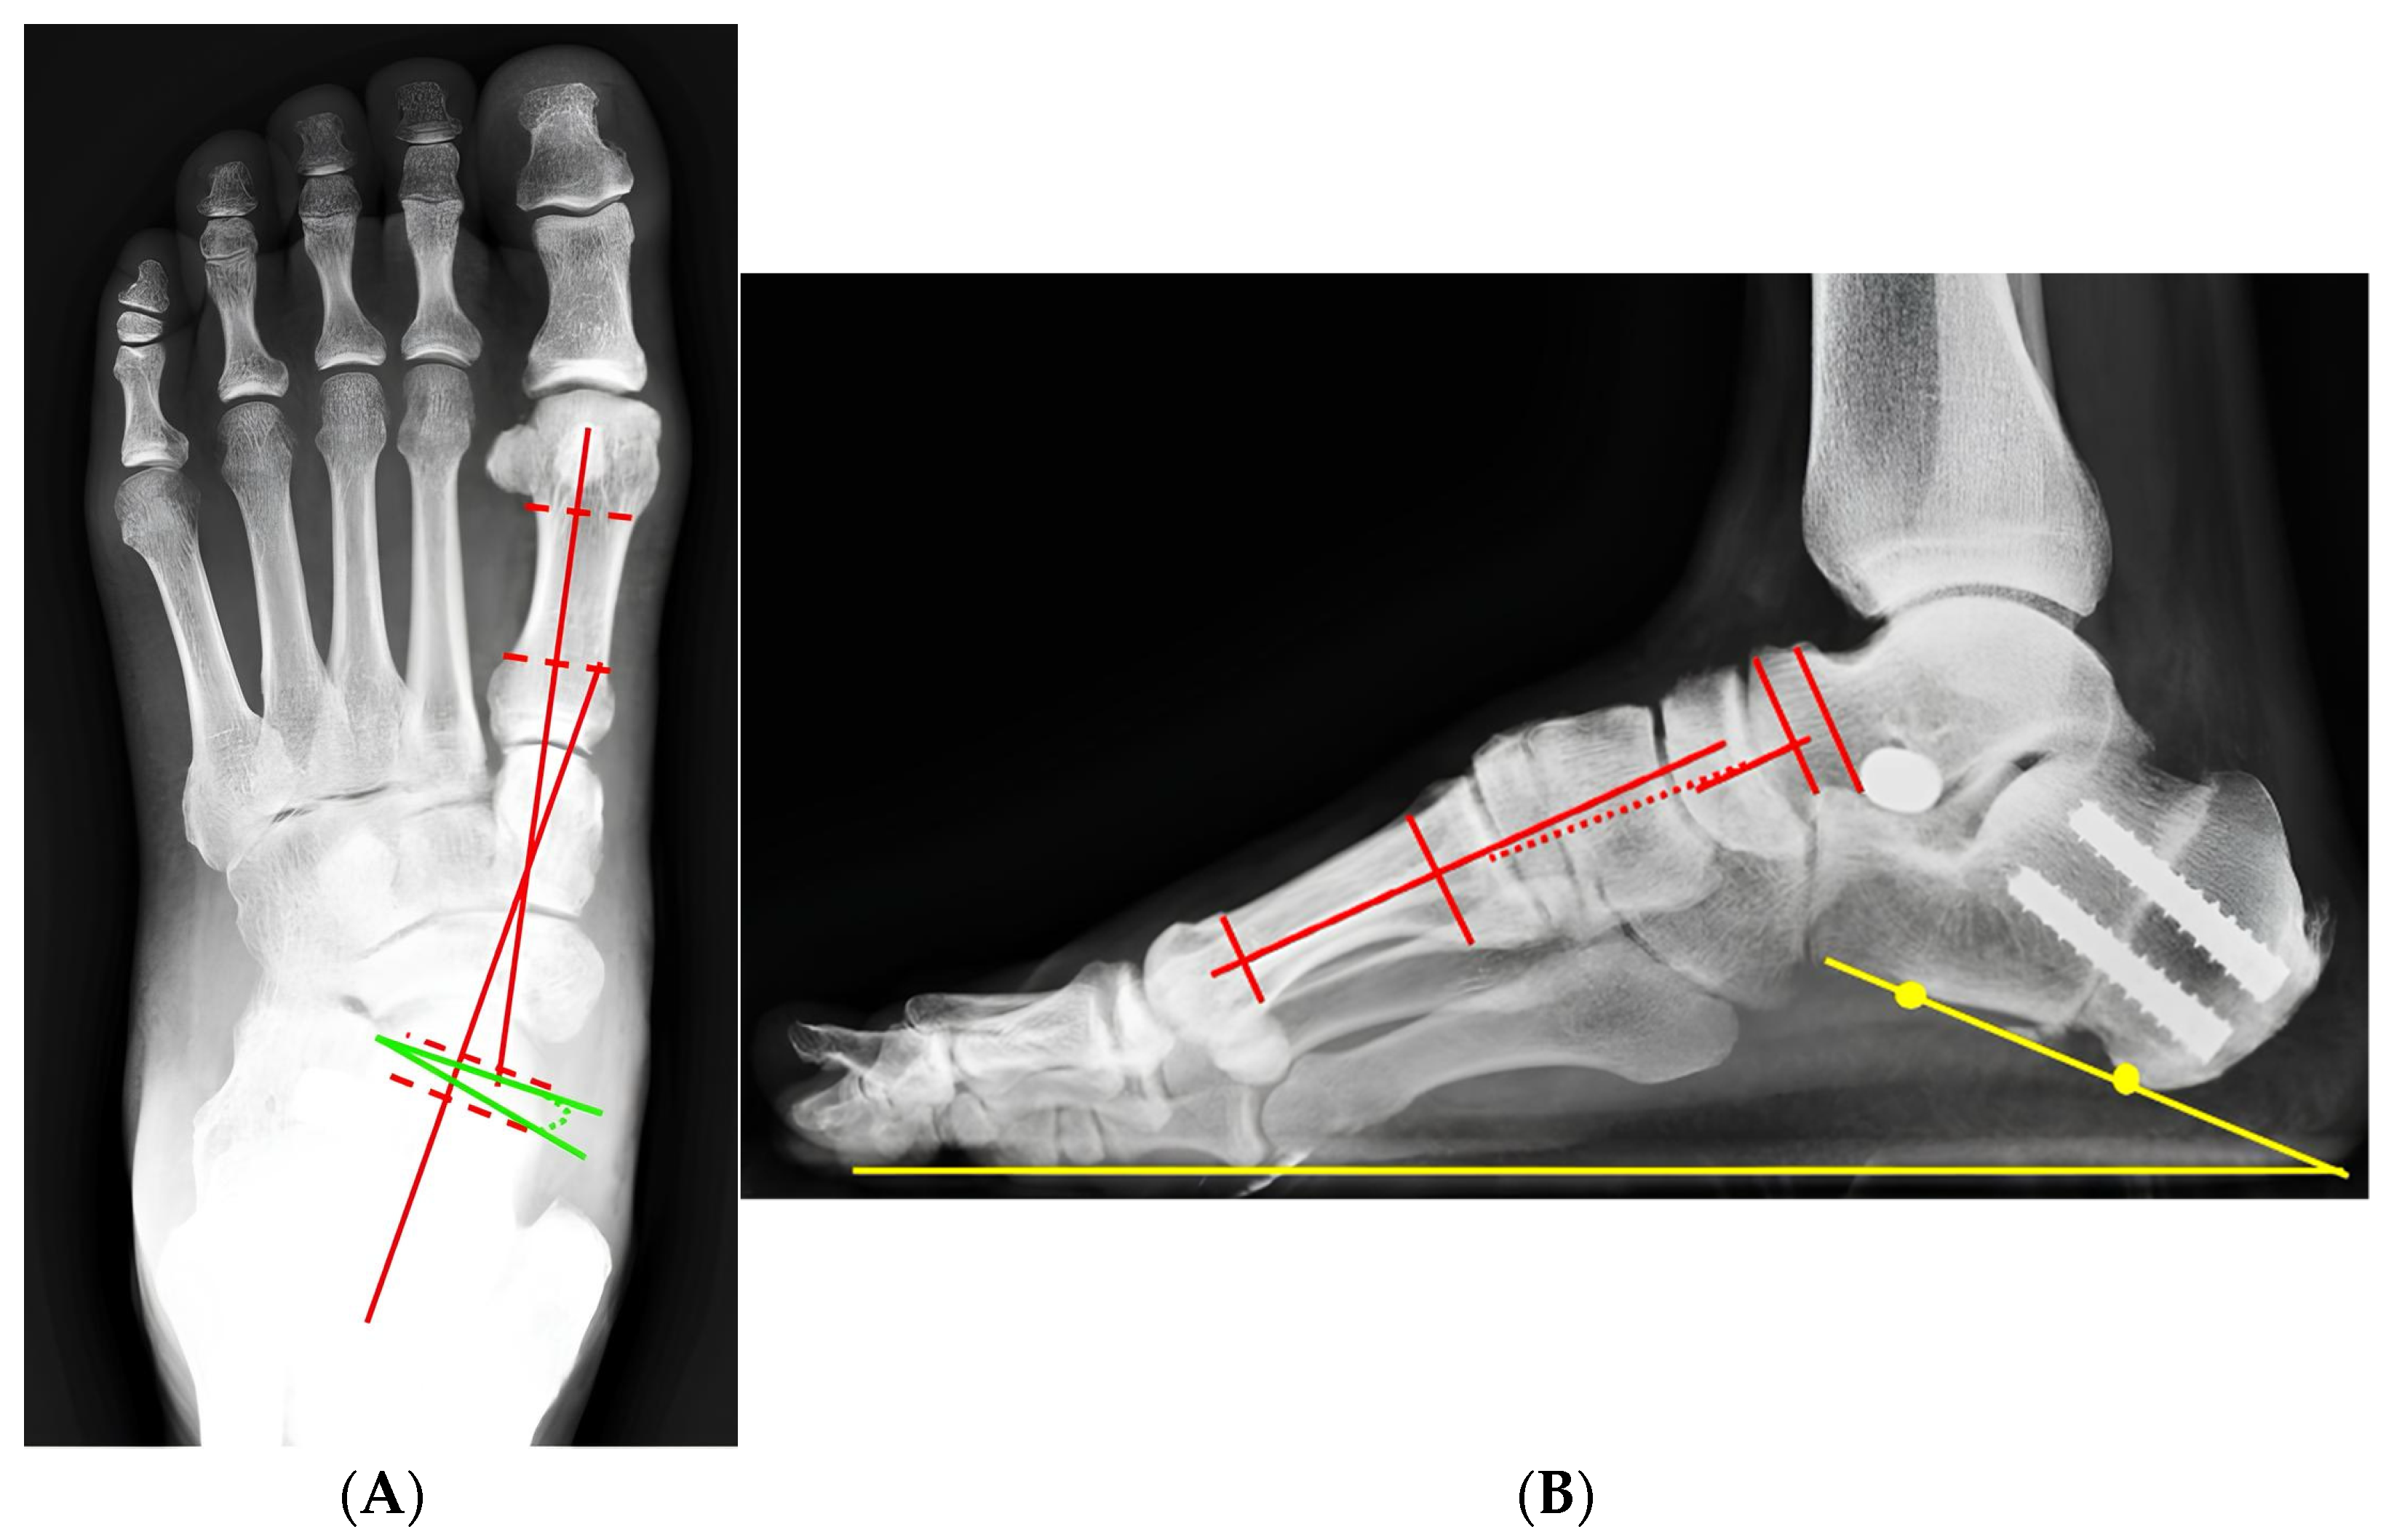

3.6. Representative Case

| Parameter | Preoperative | Postoperative | 24 Months of Follow-Up | p-Value |

|---|---|---|---|---|

| Meary angle (AP, °) | 24.2 ± 7.4 | 9.2 ± 4.1 | 8.6 ± 4.1 | <0.001 |

| Meary angle (Lateral, °) | 9.96 ± 2.3 | 1.92 ± 1.4 | 2.05 ± 1.6 | <0.012 |

| Calcaneal pitch (°) | 10.64 ± 4.87 | 15.78 ± 3.33 | 15.55 ± 4.25 | <0.01 |

| Talonavicular coverage angle (°) | 14.53 ± 6.67 | 3.46 ± 1.56 | 3.58 ± 0.78 | <0.024 |